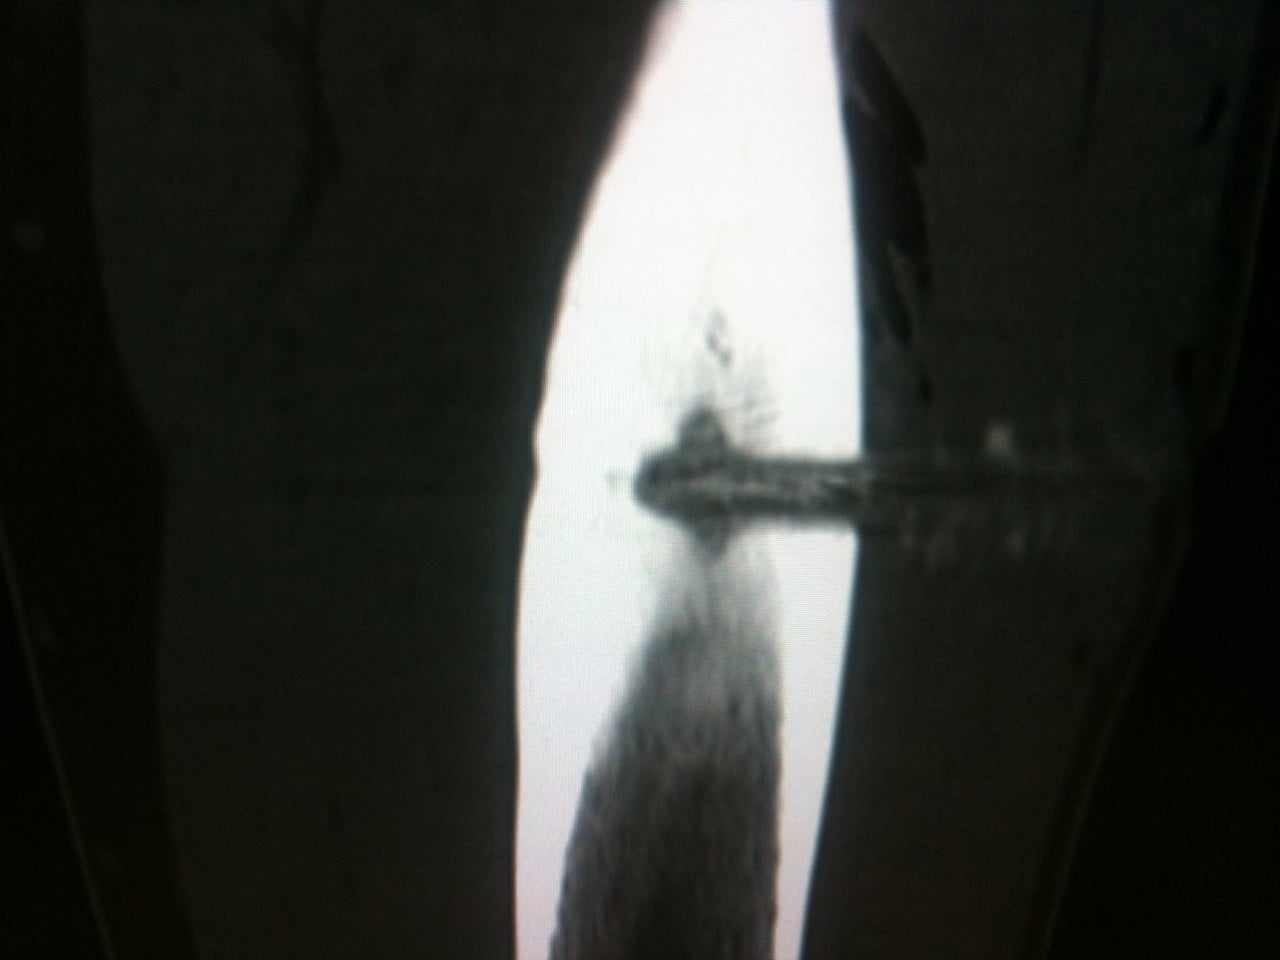

Le patient est positionné en salle de scanner interventionnel avec double guidage : scopique et scanner.

L’Examen est centré sur la région d’intérêt par Acquisition hélicoïdale de Coupes de 1 à 2mm jointives

Sous guidage scopique et scanner un trocart 11 gauges coaxial Thiebaud t’AM est introduit dans la tumeur. Le contrôle itératif par scanner permet de positionner au plus près le matériel. Cette technique évite une ouverture cutanée mais surtout permet de conserver la structure osseuse adjacente et s’assure d’une précision optimale.